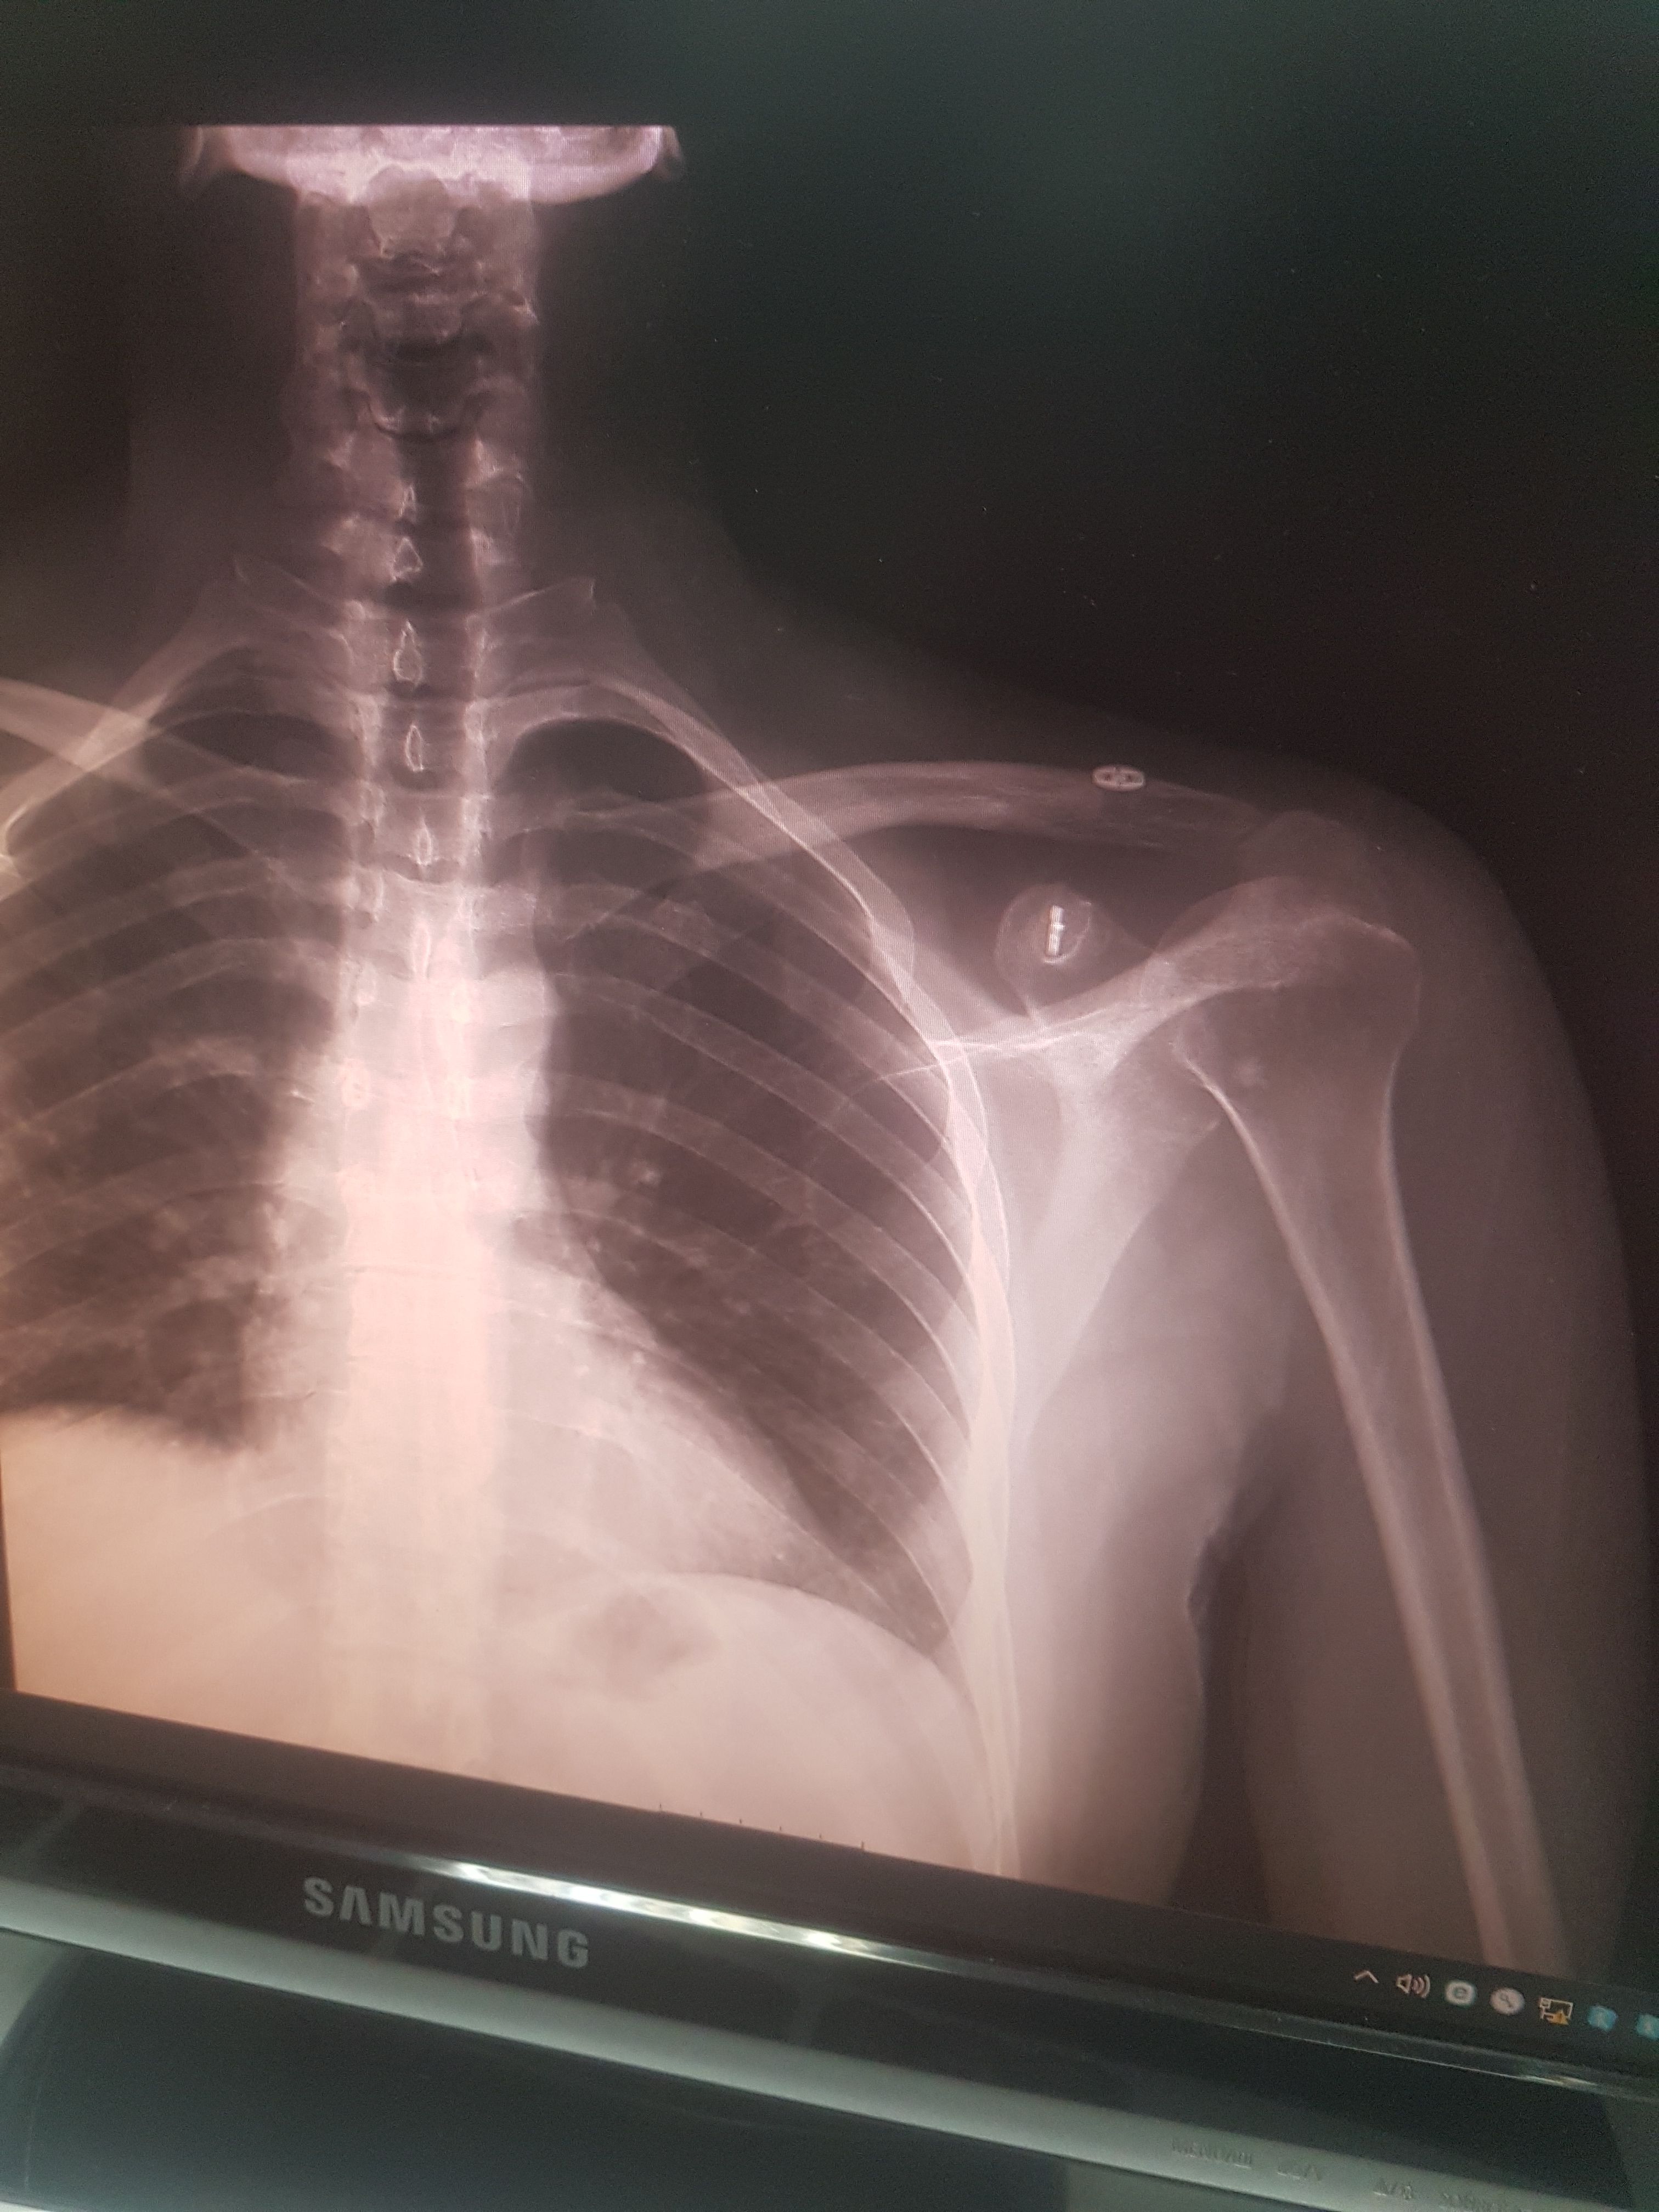

@caglar14 Aynı ameliyatı oldum 3. ay sonunda ip koptu. Çok sinirim bozuldu. Şimdi kemik yukarıda duruyor. Sadece benim mi başıma geliyor derken demek ki olabiliyormuş. Bir prof bana sağlam malzeme kullanmama kaynaklı demişti. Anlattığına göre ton kaldıran ip nasıl kopar mış ? Ya iyi tutturamadılar yada malzeme kötü dedi. Arada bir daha operasyon yaptırsam mı diyorum ama alıştım da. Siz bıraktınız mı öyle.